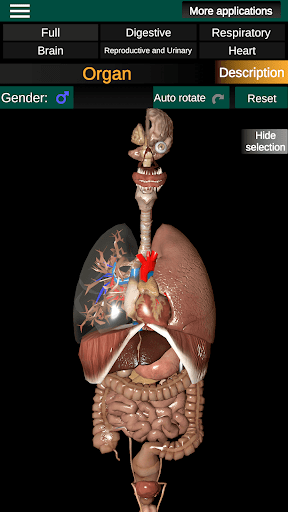

Toont een 3D-anatomisch model van de belangrijkste organen van het menselijk lichaam en een beschrijving van elk orgaan.

Wat zit er in de app?

* Gemakkelijk te openen en te navigeren (zoom, 3D-rotatie).

* Verberg of toon informatie.

* Vergelijk mannelijke en vrouwelijke organen.